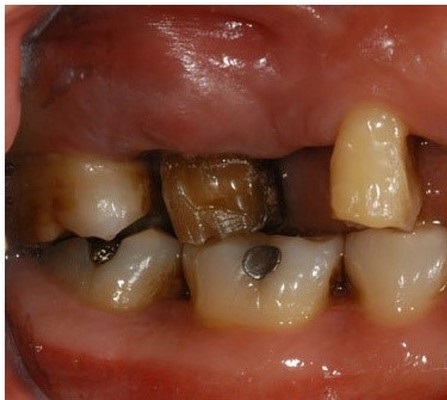

02 심하게 시행된 충치에 의해 치아를 발치 해야 하는 분

치아의 신경통은 인간이 느끼는 고통 중 손에 꼽을 만큼 고통스럽습니다. 어금니 주변에는 다양한 신경들이 많이 있기 때문에 정밀하고 세밀한 관리로 신경뿐 아니라 주변 조직의 손실을 덜어내는 것이 중요합니다.